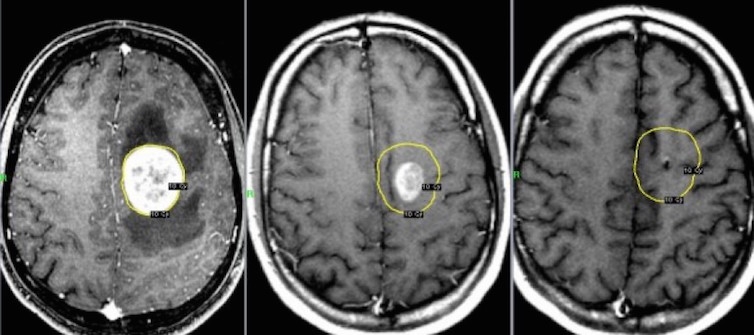

С ранна диагноза и правилно лечение обаче пациентите могат да се излекуват в 80 на сто от случаите, казва доц. д-р Берин Пехливан. В зависимост от случая, в лечението може да се използва един метод или комбинации от всички методи - хирургия, химиотерапия и лъчетерапия. Много ефективен метод на лъчелечение е томотерапията, посочва доц. Пехливан от „Медикал парк“.